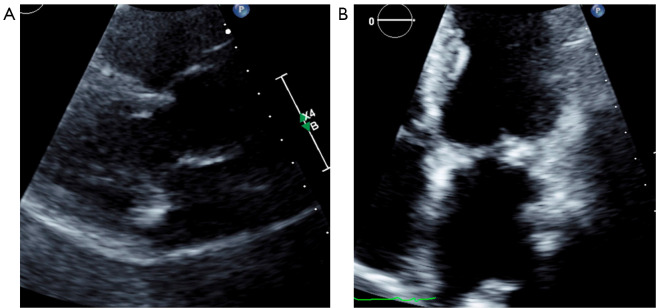

背景和目的:最近主要的国际社会指南强调了多模态成像在感染性心内膜炎(IE)评估中的应用。本文旨在通过实际案例讨论多模态成像在IE中的当代应用,展示如何使用新兴的成像方式,包括心脏计算机断层扫描(CCT)和核成像技术。方法:检索PubMed数据库2024年01月01日至2024年10月01日的文献。我们的综述使用了有关“感染性心内膜炎”和“多模态成像”的相关文章。从克利夫兰诊所基金会的四个临床病例被纳入补充这一文献综述与现实世界的例子。主要内容和发现:本文献综述包括国际心脏病学指南、调查研究、荟萃分析和专门的综述,重点介绍了不同成像方式在IE评估中的具体作用、优势和劣势,包括经胸和经食管超声心动图(TEE)、CCT、18f -氟脱氧葡萄糖正电子发射断层扫描(18F-FDG PET)和白细胞单光子发射计算机断层扫描(WBC SPECT)。这篇综述表明,鉴于越来越复杂的患者群体和越来越多的假体瓣膜和装置,这些多模态成像工具的新兴作用。结论:本文结合复杂的临床病例,讨论了目前的文献和指南,目的是说明多模态心脏成像在IE中的相对优势和劣势,以及适当的应用。

Background and objective: Recent major international society guidelines have highlighted the utility of multi-modality imaging in the evaluation of infective endocarditis (IE). This article aims to discuss the contemporary applications of multimodality imaging in IE through real-life cases, demonstrating how emerging imaging modalities, including cardiac computed tomography (CCT) and nuclear imaging techniques can be used.

Key content and findings: This literature review encompasses international cardiology guidelines, as well as investigational studies, meta-analyses, and dedicated reviews highlighting the specific roles, strengths, and weaknesses of different imaging modalities in the evaluation of IE, including transthoracic and transesophageal echocardiography (TEE), CCT, 18F-fluorodeoxyglucose positron emission tomography (18F-FDG PET), and white blood cell single-photon emission computed tomography (WBC SPECT). This review demonstrates the emerging role for these multi-modality imaging tools in light of an increasingly complex patient population with growing numbers of prosthetic valves and devices.